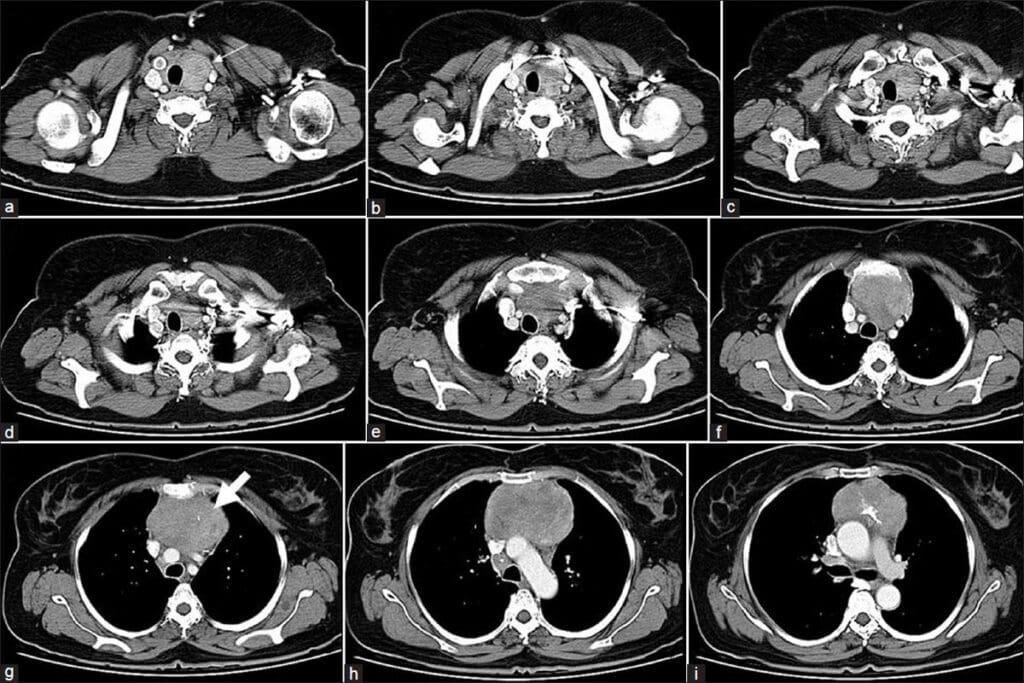

Phases of a CT Urogram Examination

A CT urogram has several phases, each showing the urinary tract at different times. The non-contrast phase gives us a starting point. The nephrographic phase focuses on the kidney’s inner parts. The excretory phase shows how the contrast moves through the system, highlighting any blockages or issues.

Dual-Phase CT Protocols (With and Without Contrast)

Dual-phase CT protocols scan the patient with and without contrast. This gives us a detailed look at the body’s anatomy and any problems. It’s great for complex cases needing multiple contrast phases.

By mixing non-contrast and contrast-enhanced CT scans, we get a full picture of the patient’s health. This helps us make more accurate diagnoses and treatment plans.

Imaging Protocol Variations

CT urogram is designed to check the urinary tract. It has several phases, starting with a non-contrast phase and then contrast-enhanced phases. Standard CT scans, on the other hand, can be set up for many different needs. They might use non-contrast or contrast-enhanced protocols.

- CT urogram has multiple phases for detailed urinary tract images

- Standard CT scans might have just one phase, depending on the need

- CT urogram focuses on the urinary tract, while standard CT scans can look at different body parts